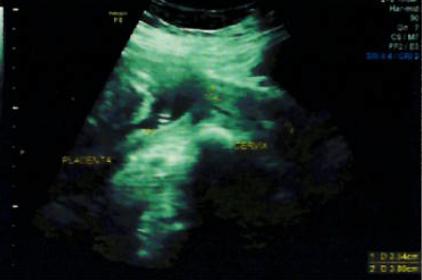

Attachment 28066Attachment 28067Attachment 28067